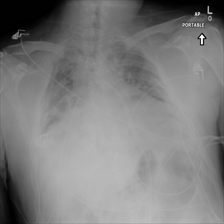

To pre-train a high-performance X-ray foundation model, the first thing we need to do is the collection of large-scale X-ray images. Therefore, a large-scale and high-resolution dataset that contains X-ray medical images is collected for the pre-training. Some representative samples are visualized in Fig. 3.